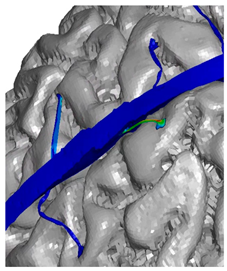

| Frontal veins | ![]() | ![]() | ![]() |

| Parietal veins | ![]() | ![]() | |

| Occipital veins | ![]() | ![]() |